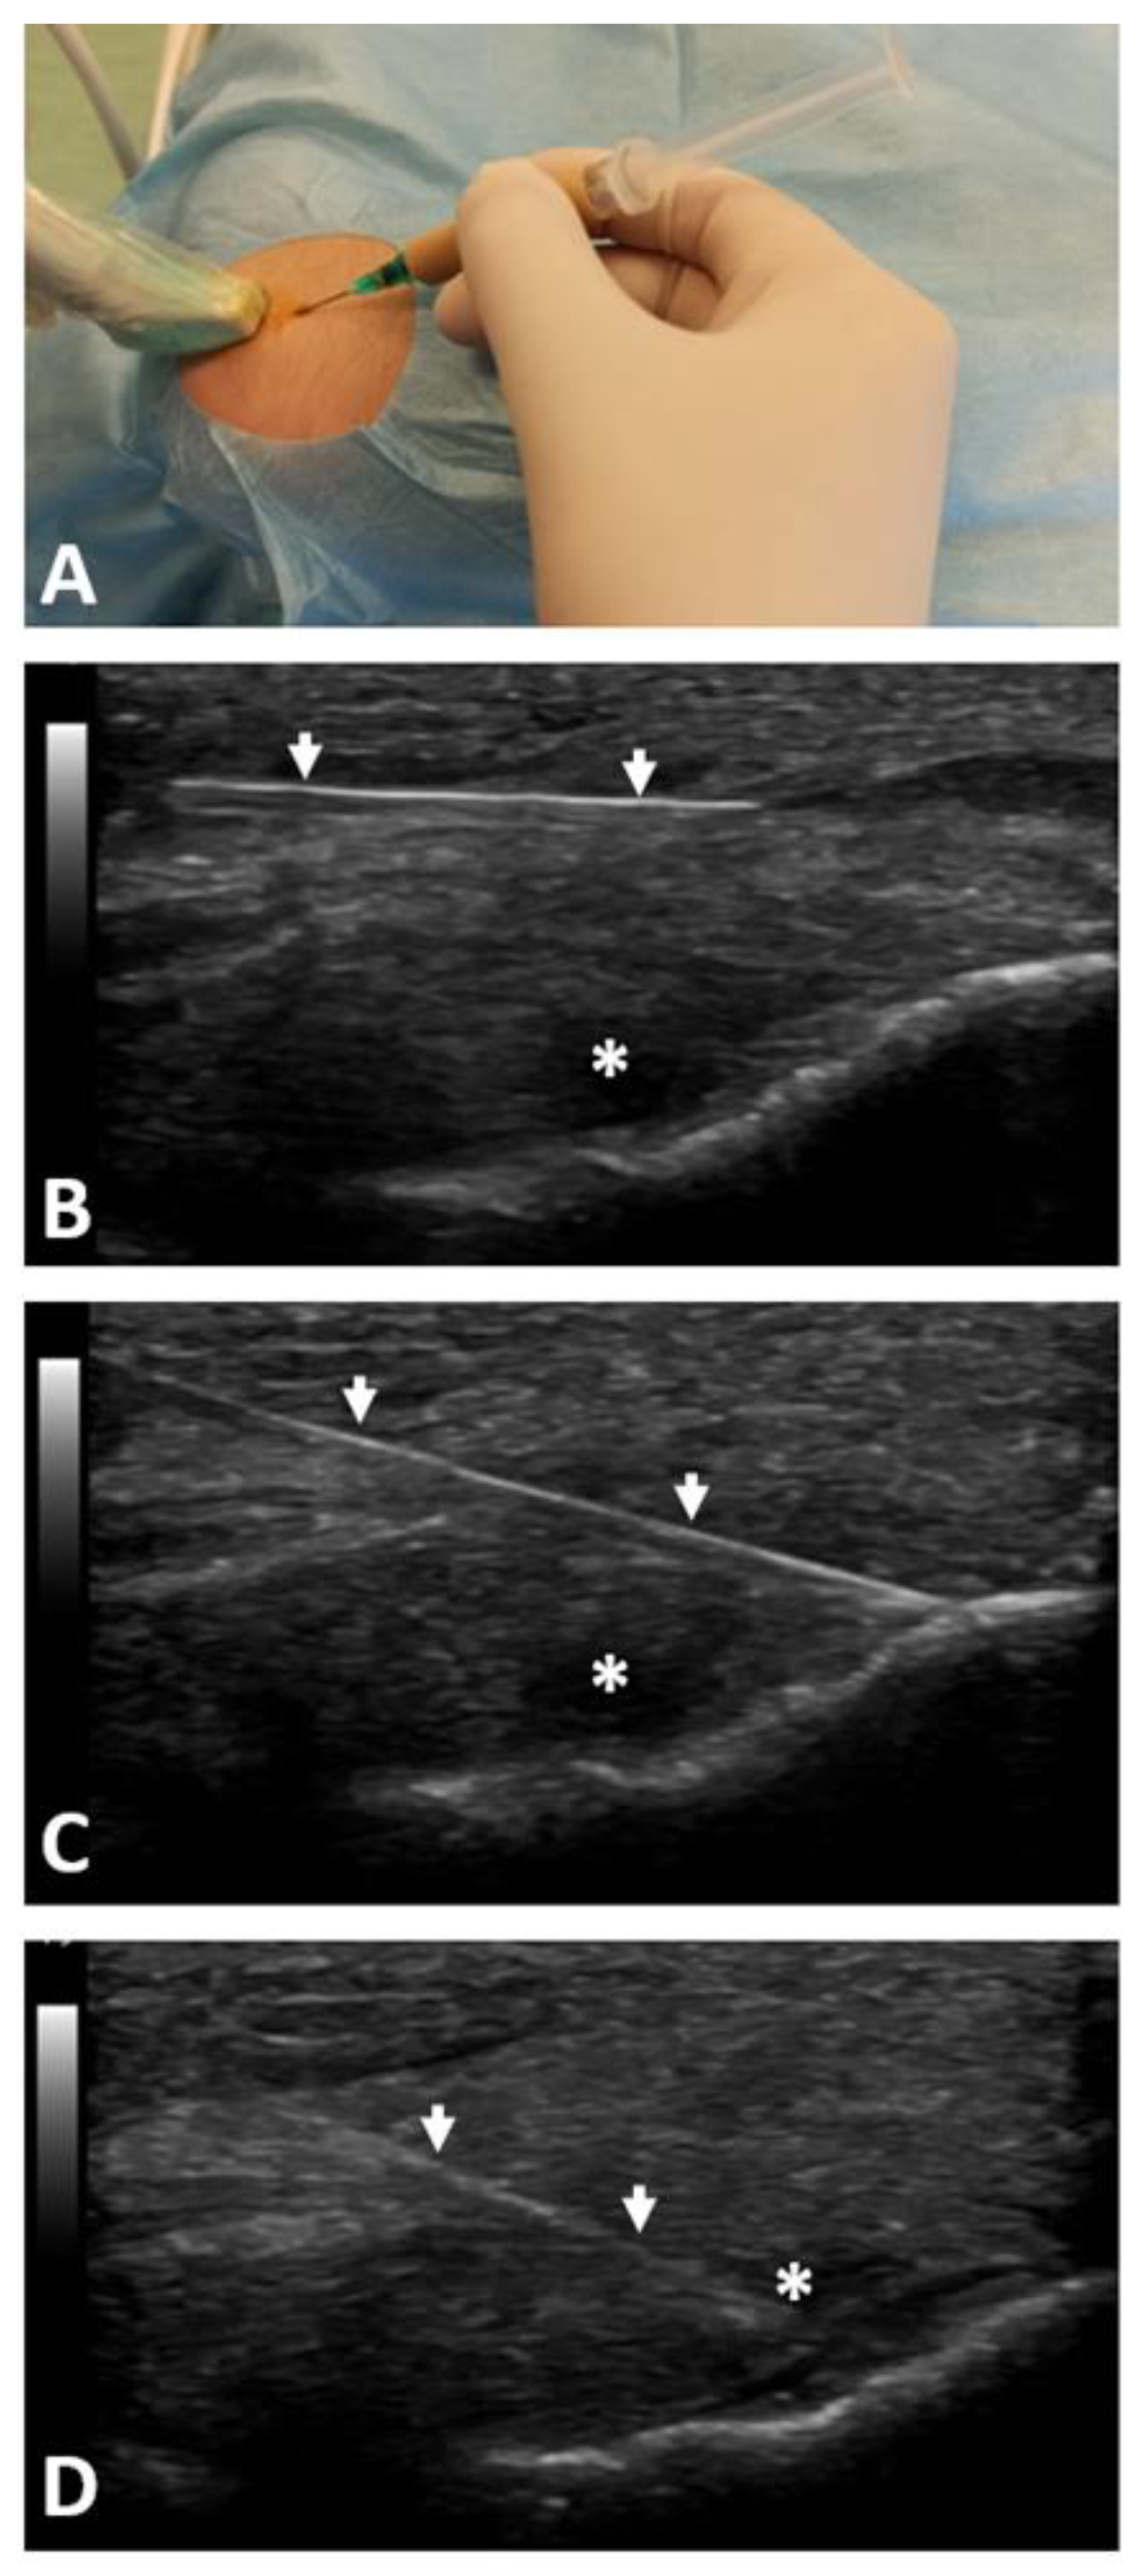

Five minutes before the injection of PRP, 1–2 mL of local anesthetic (1% lidocaine) was injected subcutaneously into the epicondyle region. Then, under aseptic conditions, under the guidance of ultrasonography, 2 mL of non-activated, liquid LR-PRP was injected into the ECRB and CE attachment to the lateral humeral epicondyle using the peppering technique from one access through the skin and with multiple punctures (approximately 10 times) through the fascia to the periosteum. The PRP was injected above and under the fascia and into the tendon lesions identified with the ultrasonography. The 21G needle was used for that purpose. A sterile dressing was applied (see Figure 3). After injection, the patients were observed for approximately 30 min. Patients were instructed to avoid overloading activities and to start stretching exercises after a week from the injection. The inclusion of eccentric exercises to strengthen the extensors of the forearm was recommended in the case of a pain reduction below three on the visual analogue scale (VAS), not earlier than two weeks after the intervention.

Figure 3.

Presentation of ultrasound-guided PRP injection technique into common extensor tendon: (A) point of skin puncture with a needle guided by ultrasound probe in sterile conditions; (B) injection of 1–2 mL of 1% lidocaine in the subcutaneous region; (C) the peppering technique with multiple needle punctures through the fascia to the periosteum; (D) PRP injection into the hypoechogenic region of ECRB. PRP—platelet-rich plasma; ECRB—extensor carpi radialis brevis; arrows—view of the needle position under ultrasound; *—hypoechogenic region of the tendon.